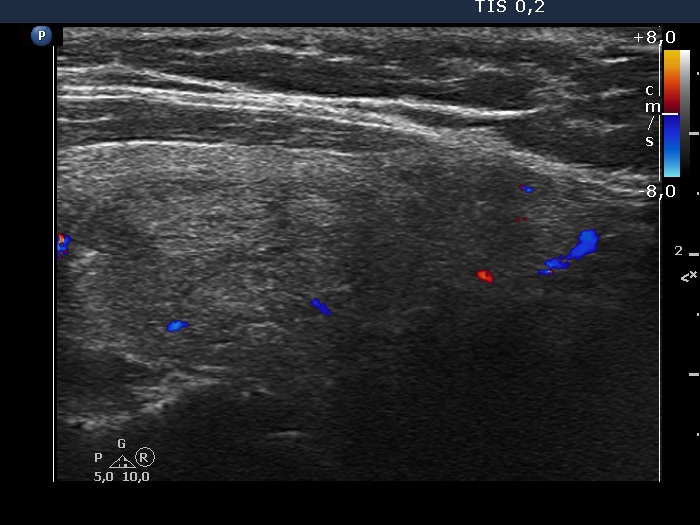

Right lobe, longitudinal scan

Left lobe, longitudinal view, color Doppler mode. The vascularization is scanty.